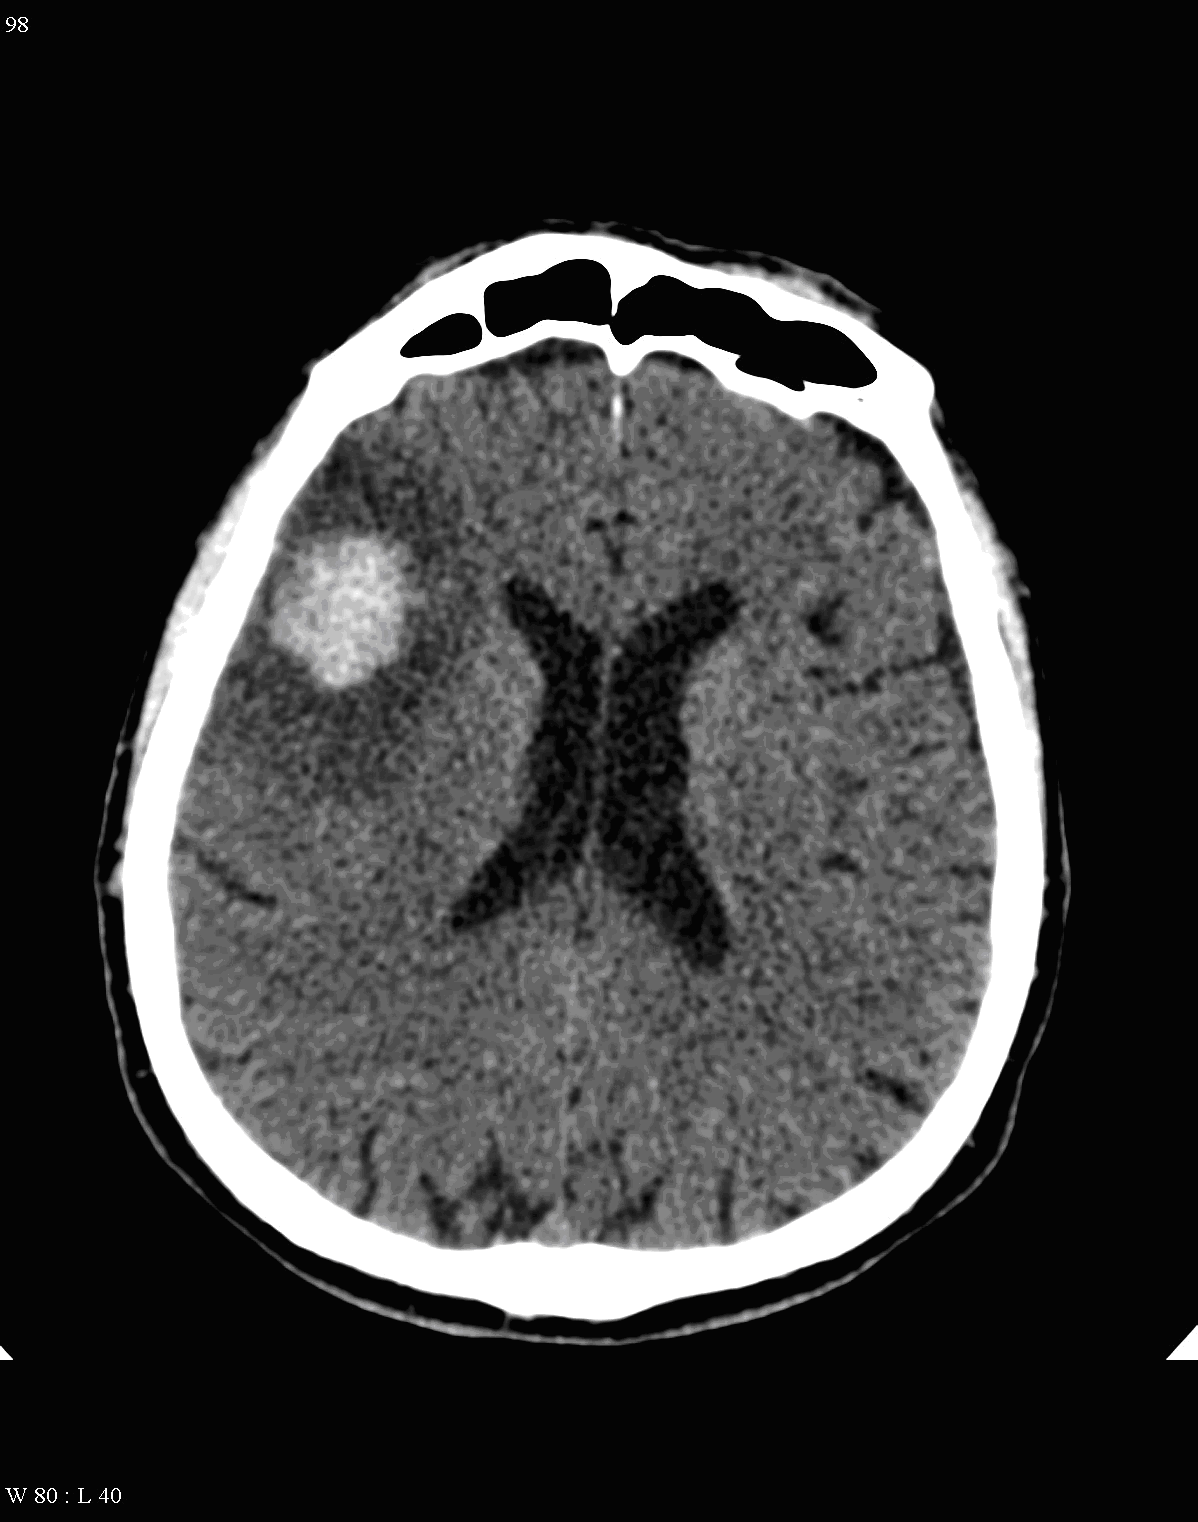

On CT images acute bleeding always presents as hyperdensity. (One has to keep it mind that hyperdensity of the blood is affected by the hematocrit levels, hence making the diagnosis more difficult.) Intraparenchymal blood is dominated by a destructive appearance (mass-effect) and it is surrounded by hypodensity as a sign of perifocal edema. It often breaks into the ventricles. In patients lying in a supine position they collect (sediment) at the occipital horn of the lateral ventricles, creating a hyperdense liquid-to-liquid levels. Later on, the density of blood decreases and shows a peripheral ring or rim-like contrast enhancement without mass-effect.

Parenchymal hemorrhage most often occurs in patients with hypertension, after malignant hypertensive states. The initial localization for its occurrence is at the basal ganglia (putaminal-claustral hemorrhage) that can extend into the ventricles or to the subarachnoid space. The mean age of these patients is usually younger than that of the ones with ischemic infarcts.

Hemorrhagic infarcts make up 15% of strokes. The underlying cause is usually hypertension, but vascular malformation, aneurysm rupture, cerebral amyloid angiopathy, tumor bleeding and the hemorrhagic transformation of ischemic infarcts can all lead to cerebral hemorrhage. Moreover - as a rather common cause - patients with coagulopathies (mostly the ones receiving antithrombotic therapy) can also suffer hemorrhagic stroke.